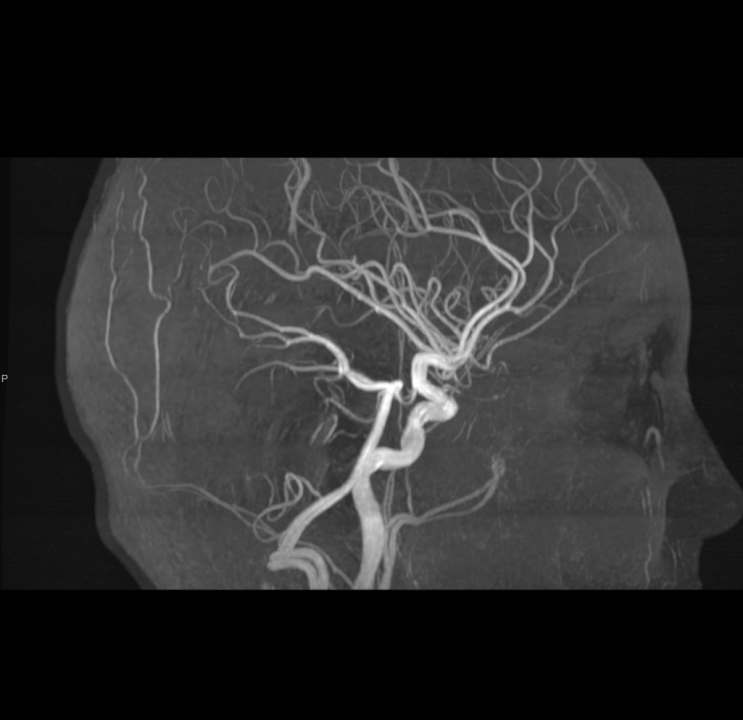

Tijekom Tjedna mozga Poliklinika Affidea Vita daje 20 posto popusta na magnetsku rezonancu!

Povodom obilježavanja Tjedna mozga od 11.